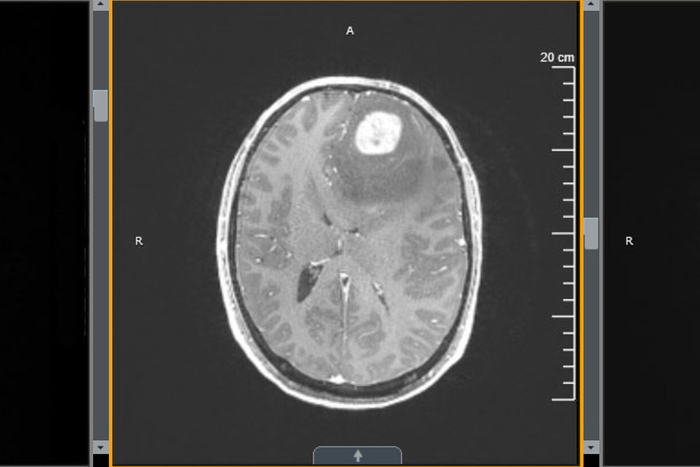

A new study from Washington University School of Medicine in St. Louis shows that treatment with an immune-boosting protein called interleukin 7 (IL-7) in combination with radiation improves survival in mice with glioblastoma. Shown is an MRI scan of the brain of a patient with glioblastoma.